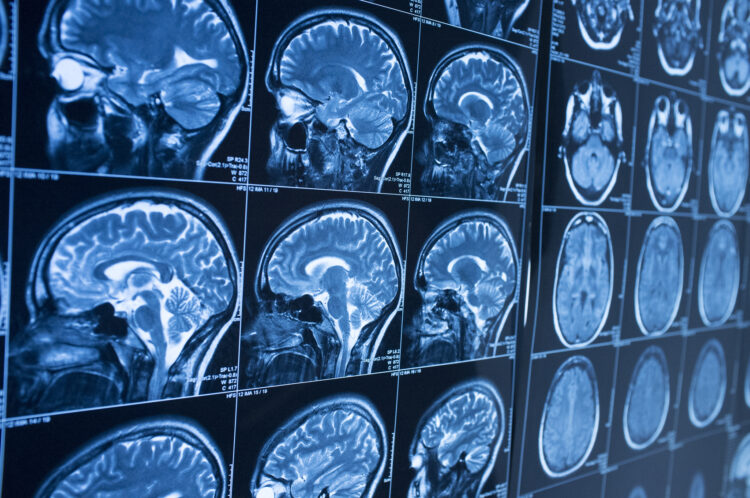

Mild TBI sounds minor. It’s not. Concussions disrupt brain function even when imaging tests show no visible damage. You might experience headaches, dizziness, memory problems, difficulty concentrating, mood changes, and sensitivity to light or noise.

These symptoms sometimes resolve within weeks, but they may persist for months or years, creating what medical experts call post-concussion syndrome. The invisible nature of these injuries makes insurance companies skeptical, but the impact on your life remains very real.

Insurance adjusters may see normal CT scans or MRIs as proof you’re not really injured. However, mild traumatic brain injuries may cause functional problems without visible structural damage. Concussions disrupt how brain cells work, not necessarily how they look on imaging.

Neuropsychological testing reveals cognitive deficits that imaging misses. These detailed assessments measure memory, processing speed, executive function, and other cognitive abilities that are affected by brain injuries. The testing provides objective evidence of impairments that explain why you struggle with tasks that used to be easy.